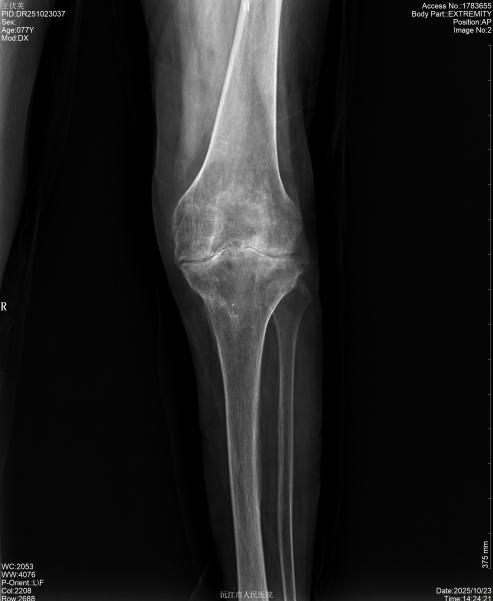

77岁患者的困境则聚焦于技术攻坚。罹患类风湿性关节炎长达40年,近5年膝关节病变加剧,膝关节软骨磨损严重、关节僵硬畸形,日常动作皆伴剧痛,夜间无法入眠。同时患有高血压、糖尿病。直至生活无法自理时,才将希望寄托于沅江市人民医院。

手术中,骨外一科(脊柱、关节、骨病、运动医学)团队针对两位患者的不同痛点,精准施术、高效攻坚。为94岁患者实施人工髋关节置换术时,团队从切口显露、股骨取出,到假体植入,每一步都精准操作,仅50分钟顺利完成手术。为77岁患者开展全膝关节置换术时,团队严格把控截骨角度、精细调整软组织平衡,精准安装假体,手术历时1.5小时,出血量仅200ml,远低于常规水平,最大程度降低了患者创伤。

手术成功只是起点,术后康复是回归正常生活的关键。护理团队为两名患者量身定制康复计划,从早期被动活动到后期行走训练,全程精细化指导。恢复速度远超预期:94岁患者术后第3天即可借助助行器下床并缓慢行走;77岁患者术后第3天,疼痛评分(VAS评分)从8分降至2分,术后两周便能独立完成日常动作,顺利康复出院。